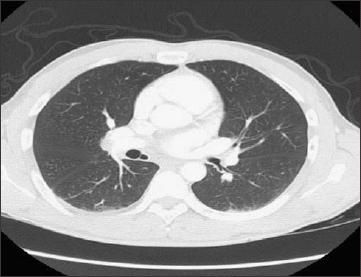

Laboratory values revealed a leukocytosis with a white blood cell count of 17,000/μL and a neutrophil predominance. Other laboratory findings, including toxicology screening results, were normal. A CT scan of the chest was obtained (Figure 1). The patient subsequently underwent bronchoscopy (Figure 2).

Figure 1

The patient's CT scan showed an anomalous bronchus arising from the medial wall of the bronchus intermedius and descending inferomedially toward the heart. However, no pulmonary parenchyma was seen surrounding the bronchus. Based on its location, this anomaly was identified as an accessory cardiac bronchus.